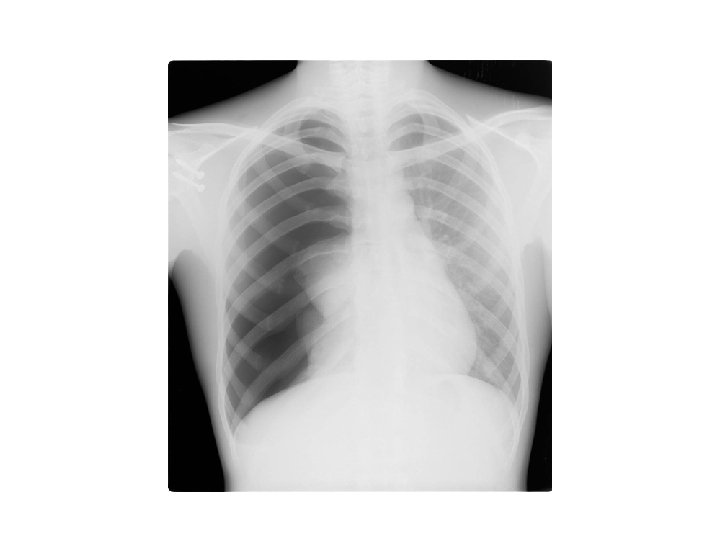

Cas clinique 3 • Femme, 45 ans • Douleur thoracique gauche • Dyspnée progressive, insp • ATCDT K sein droit 5 ans: TTT chir et radiothérapie • MV base gauche

Diagnostic évoqué ? Conduite à tenir diagnostique ? Conduite à tenir thérapeutique initiale et en cas de récidive ?